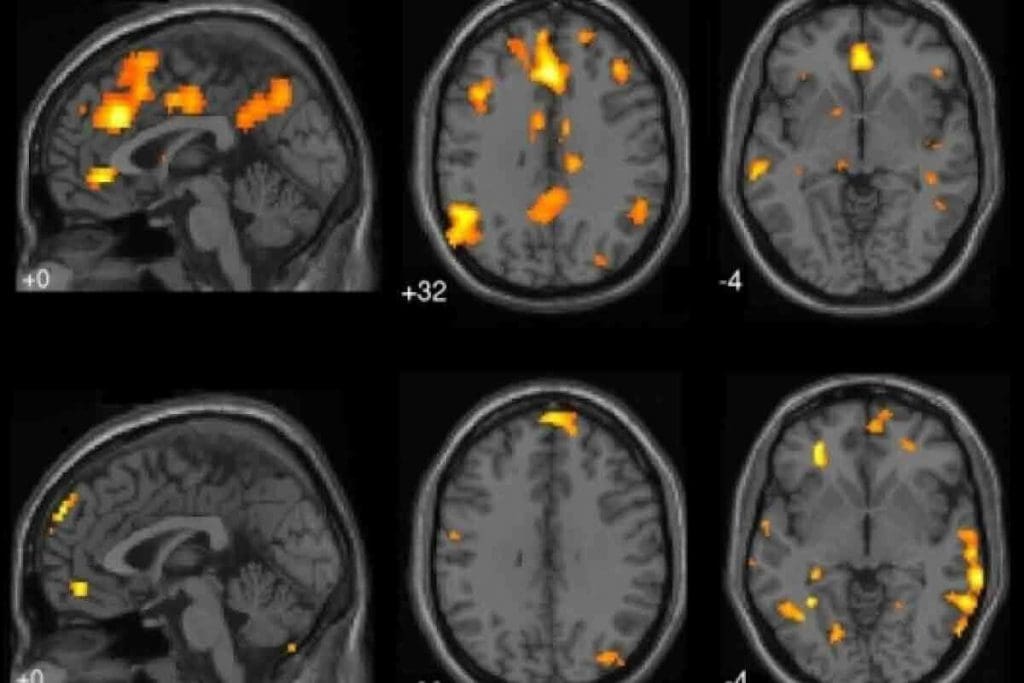

CT Perfusion Imaging Applications

CT perfusion imaging is a key tool for brain tumor evaluation. It shows us how tumors grow and how well they block blood flow. A study in Nature found it can tell the difference between a tumor coming back and damage from treatment.

Key applications of CT perfusion imaging include:

• Monitoring treatment response

Computer Vision-Based Segmentation

Computer vision-based segmentation is another advanced method for brain tumor assessment. It uses artificial intelligence to make tumor identification more accurate and quicker.

Linking CT scans with molecular profiles is key in brain tumor evaluation. This mix of imaging and genetics helps doctors understand tumors better and plan treatments.

The future of brain tumor diagnosis is combining advanced CT techniques with molecular profiling. This will lead to more personalized and effective treatments.